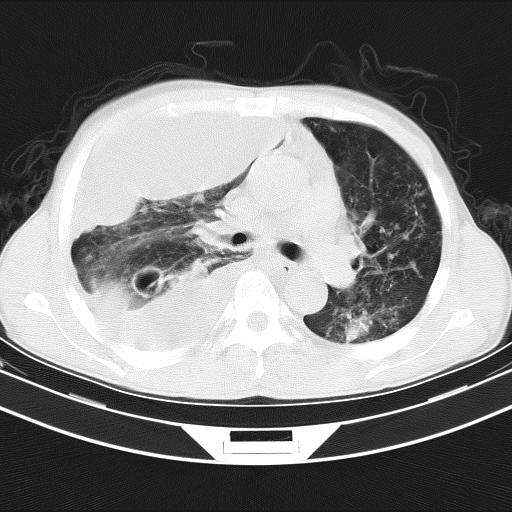

男性,44岁,结核病史多年。现胸闷气短,咳嗽,偶咳血。

1)两肺继发性肺结核伴空洞形成,左肺多发性结核球。2)右侧大量胸腔积液伴右肺部分膨胀不全。3)纵隔淋巴结肿大。

支持1)两肺继发性肺结核伴空洞形成。2)右侧大量胸腔积液伴右肺部分膨胀不全。3)纵隔淋巴结肿大。